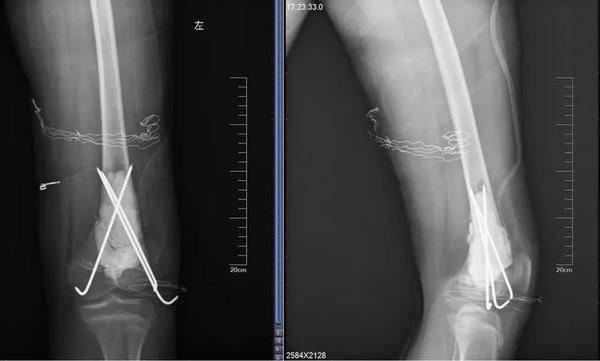

12岁的男孩儿浩浩,在学校上体育课,扭伤后突发右侧大腿剧烈疼痛,不能活动,被家人紧急送到医院,当地医院拍片后提示右股骨中下段斜行骨折。随后,医院按照一般骨折处理。

当地医生将病理组织送河南省肿瘤医院病理会诊,提示为骨肉瘤。消息犹如晴天霹雳,但更让两个孩子的父母痛苦的是,“由于按一般骨折做了手术、打了钢板和钢钉,破坏了肿瘤外面原本相对完整的包膜,这个自然屏障一旦被破坏,肿瘤细胞就会‘污染’周围组织,以后想再切干净就更困难了。”河南省肿瘤医院骨与软组织科主任、主任医师姚伟涛表示。

最终,王鑫医师组为浩浩、晨晨两位小朋友选择了新辅助化疗,待疼痛症状缓解后,手术取出钢板、钢钉,并通过扩大切除手术,完整切除长瘤子部分的股骨,并进行体外灭活,搭配肿瘤型组配人工膝关节置换,达到了既完整切除肿瘤,又保全了孩子肢体功能的目的。做到这些让孩子远离骨肉瘤骨肉瘤的致病原因目前并不明确,常认为是多种因素综合导致,比如放射性辐射、接触化学物质、基因突变等。首先,家长对于孩子出现身体异常,一定要引起重视,发现子女在不明确病因的情况下出现了骨头疼痛、关节肿痛,请及时前往医院查明病因;家长要多鼓励孩子外出进行户外运动,不要接触过多放射性辐射;另外,户外运动时,也要注意关节处的保护,提醒孩子注意运动秩序和方式,避免造成骨骼损伤及软组织拉伤。王鑫提醒,如果出现问题,怀疑骨肿瘤性疾病,尤其是合并病理性骨折,家长一定要带孩子到专业的骨肿瘤科就诊,必要时行磁共振检查,仔细甄别骨折原因!